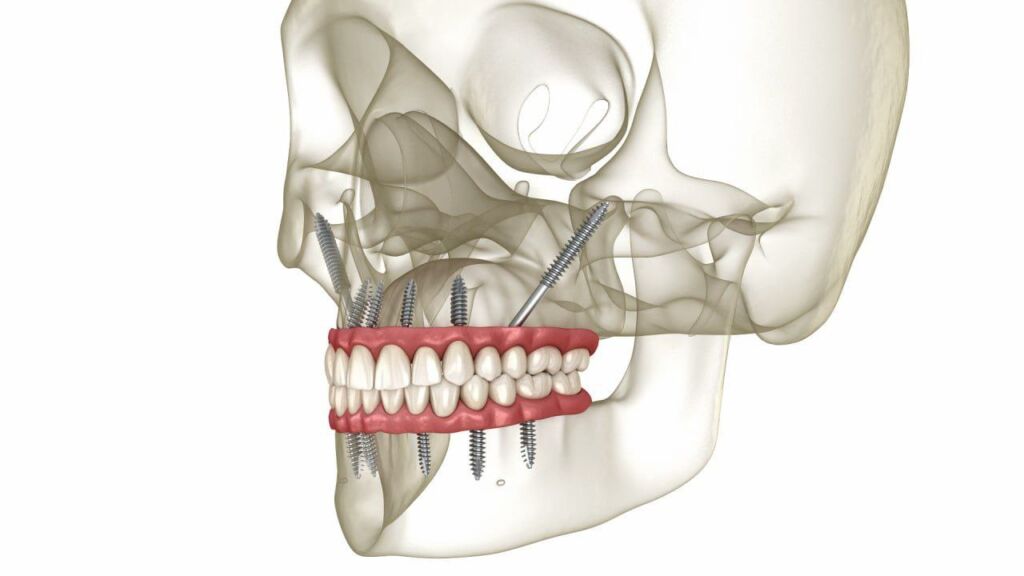

Zygomatic Implants

Zygomatic implants are a specialized option for severe bone loss in the upper jaw. Instead of anchoring only in the maxilla, these longer implants engage the cheekbone (zygoma), which can help avoid extensive grafting.

This technique is advanced and anatomy-sensitive. A systematic review and meta-analysis found high long-term survival for zygomatic implants, and also discusses complications that require careful follow-up (including sinus-related issues). [3]